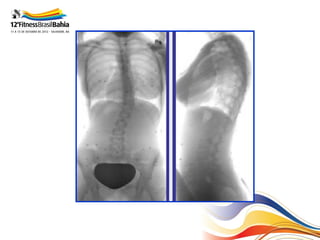

Aspectos Radiológicos

• Topografia;

• Ângulo de Cobb;

• Rotação:

– Nash-Moe

– Perdriolle

• Bending – test;

Grau de Risser

Eixo de referência

Ângulo de Cobb

Bending – Test.

Ângulo Cobb em bending

R=1-        __________________________________

Ângulo Cobb